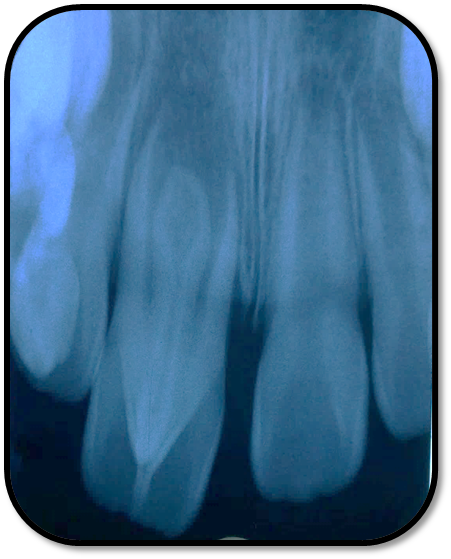

检查: 右上1牙冠略宽大,舌侧见粗大的畸形舌尖,叩痛(++),松Ⅰ°,唇侧牙龈红肿前庭沟膨隆扪痛,挤压唇侧龈缘溢脓,冷热测无反应,右侧上下1侧方颌,正中颌颌创伤。 X线:右上1发育7-8期,根管平行状,根尖孔宽大,约5-6mm宽,根尖周低密度影。髓腔根管宽大内见倒置牙影像,倒置牙可见髓腔。 余牙未见异常 6均已萌出建颌

随访复查: 治疗完成后1个月复查:右上1临床检查无阳性体征,叩痛(—),冷测无反应,无松动,牙龈无红肿,充填物完好,牙冠略有变色, X线检查:牙根根继续发育,可见钙化影像形成,如图示 治疗完成后7个月复查:临床检查无阳性体征,充填物完好,牙冠变色局部发黑,叩痛(—),冷测无反应,无松动,牙龈无红肿,临床及 X线检查:牙根继续发育,如图示 治疗完成后17个月复查:临床检查无阳性体征,充填物完好,牙冠变色局部发黑,叩痛(—),冷测无反应,无松动,牙龈无红肿。X线:牙根继续发育,根尖孔已近闭合。如图。 讨论: